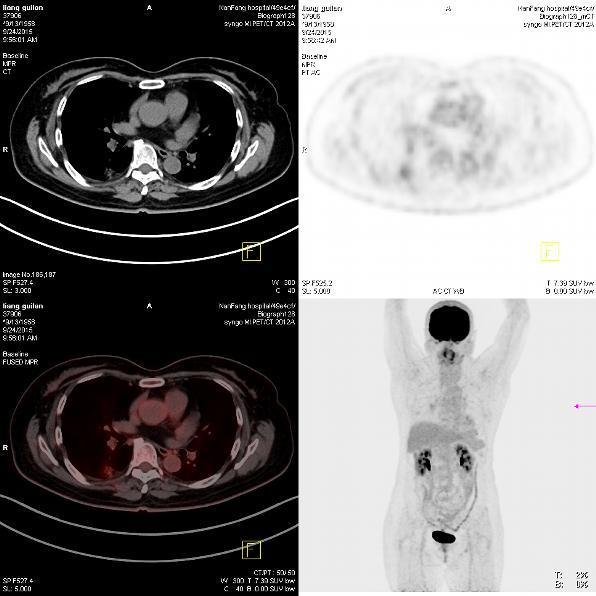

患者,女,57岁,因“右肺占位”于2015-09-17 15:08入院。 患者缘2月前体检无意发现右肺占位,伴随症状:无咳嗽、咳痰、无胸闷、胸痛、气短,无头晕、视物旋转,无恶心、呕吐,无腹痛、腹泻,无尿急、尿频、尿痛,2015-7-1 CT示:1.右肺上叶前段及下叶背段结节伴实变,右肺下叶结节见支气管气相征,考虑炎性病变可能,建议治疗后复查除外肿瘤性病变;双肺多发炎症;2.双侧胸膜肥厚;肺动脉增宽,提示肺动脉高压;3.肝左外叶小囊肿;4.甲状腺双叶增大,考虑为甲状腺肿,请结合临床。2015-9-2复查CT示:1.右肺上叶前段结节较前片无明显变化;右肺下叶背段结节较前片增大,建议进一步检查除外肿瘤性病变;双肺多发炎症较前片吸收;2.双侧胸膜肥厚;肺动脉增宽;3.肝左外叶小囊肿;4.甲状腺肿大,同前片。以“右肺占位”收住院,自发病以来,食欲减低,体重无明显下降,大小便无异常。

诊断为右肺上叶前段,下叶背段高分化腺癌,T4N0M0(IIIA)期 行胸腔镜手术楔形切除术,术后测EGFR阳性,给予分子靶向药物埃克替尼治疗

患者无任何症状,体检发现肺部小结节影,观察2月,未见缩小,似有轻度增大,入院后经CT引导下肺穿刺活检提示高分化腺癌,行手术治疗。 周围型肺癌早期影像学表现为孤立的肺内结节或肿块,通常有分叶征,毛刺征,空泡征,支气管充气征,坏死液化或空洞形成。此患者仅表现为淡薄的渗出影,小结节影,观察2月没有变化后,经穿刺证实肺癌,因此对肺部小结节影,斑片影,不吸收,无钙化的要特别注意肿瘤可能。